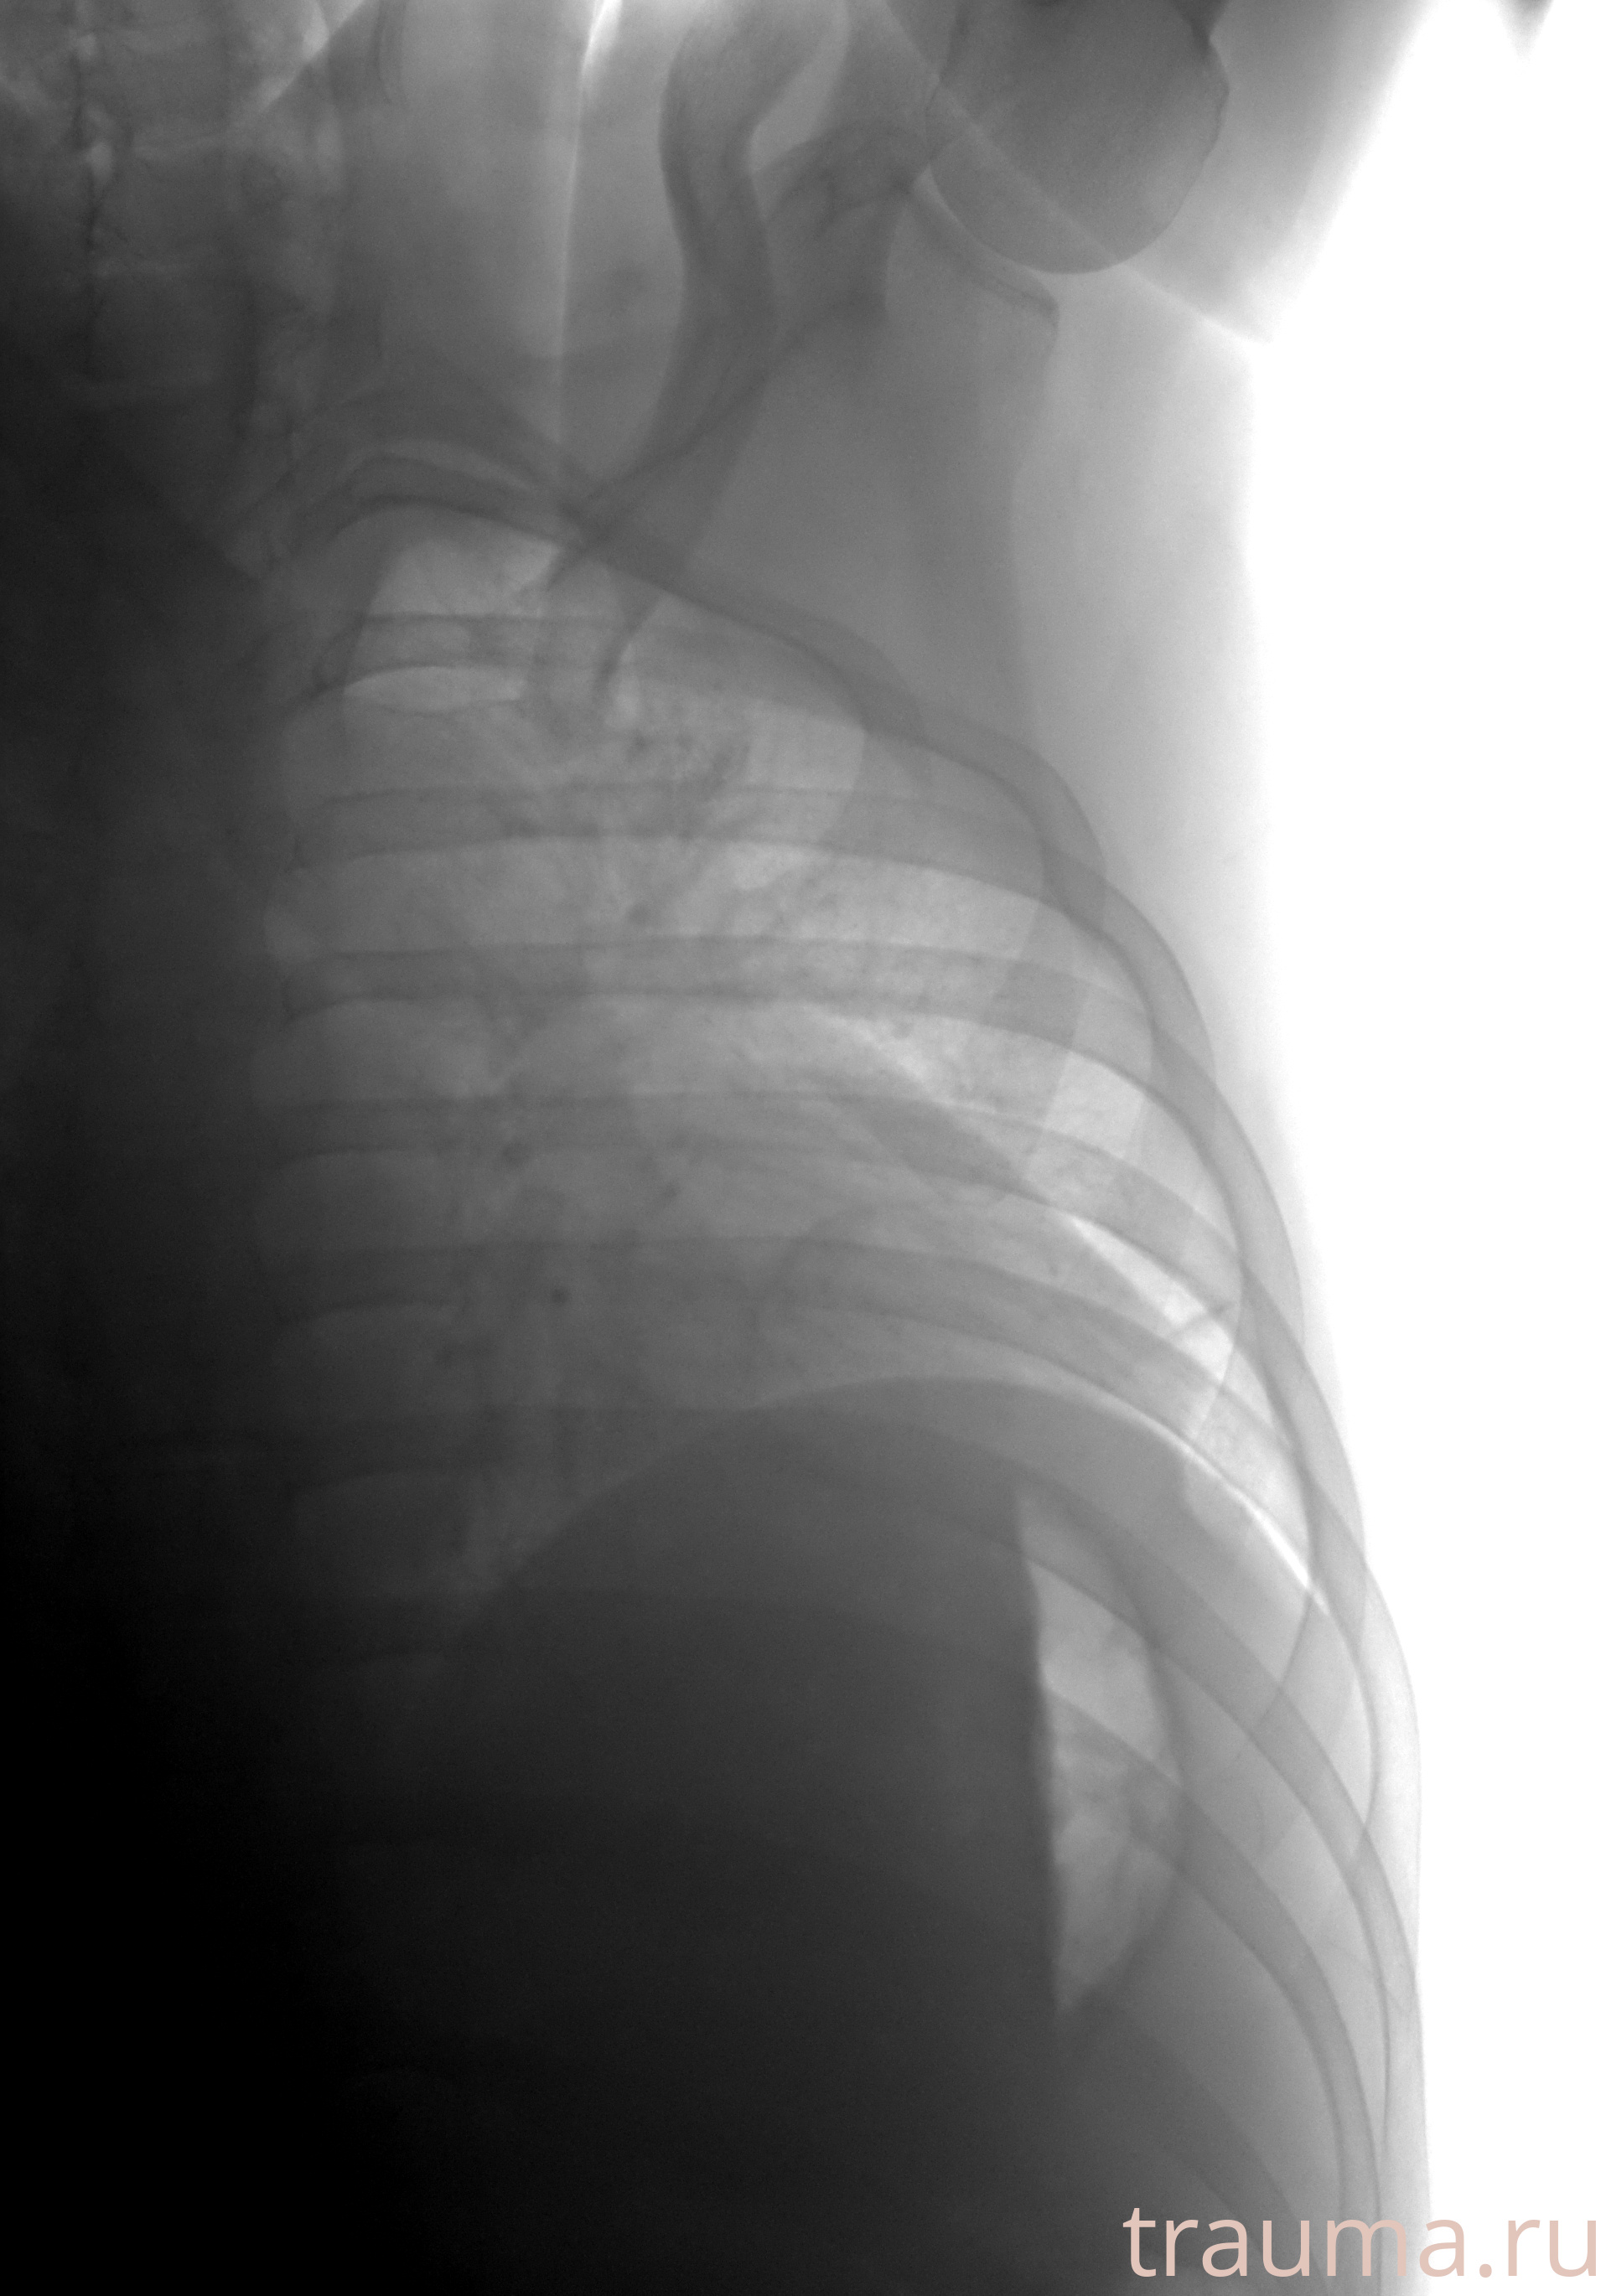

Рентгенограммы

Рентген на дому: по вашему адресу приезжает врач-рентгенолог, травматолог-ортопед с мобильным рентгеновским аппаратом, проводит диагностику травмы или заболевания, делает необходимые рентгенограммы, дает рекомендации по дальнейшему лечению. Получить качественные снимки в домашних условиях возможно благодаря уникальной методике, разработанной МосРентген Центром для института  Склифосовского